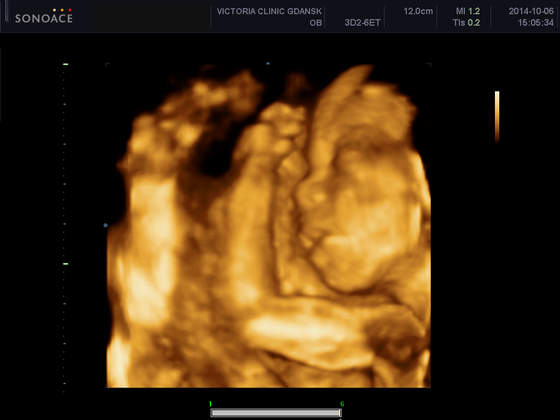

KM_0020.jpgtak sobie słodko śpię!

• KM_0020.jpg

KM_0020.jpg

20,1 KB · Wyświetleń: 137